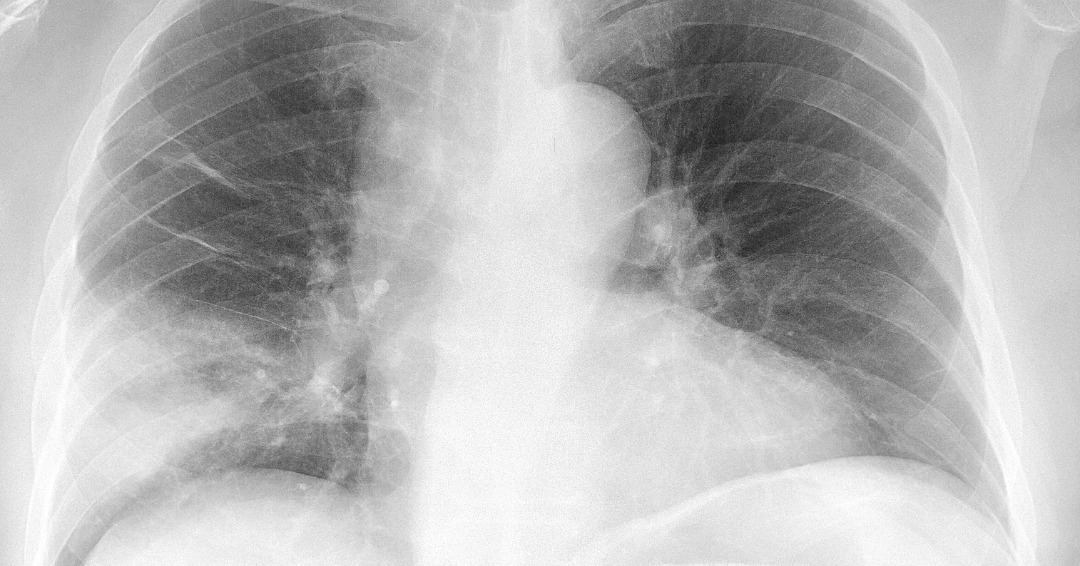

Quando se trata de pneumonia atípica, geralmente há um tipo de barulho ao respirar denominado chiado. É um som parecido com o do vento. Às vezes, radiografias de tórax também são realizadas, pois costumam revelar a infecção. Como a maioria das causas são bactérias, o tratamento mais utilizado são os antibióticos.

Uma sugestão é iniciar da periferia seguindo para as estruturas do centro, por exemplo: partes moles — arcabouço ósseo — mediastino e traqueia — hilos e trama vascular pulmonar — cúpulas e seios costofrênicos — coração e aorta). OS ACHADOS DE IMAGEM: no contexto de uma pneumonia, caracteristicamente encontramos áreas de.

APRENDA COMO IDENTIFICAR UMA PNEUMONIA ATÍPICA NO RAIO X DE TÓRAX YouTube